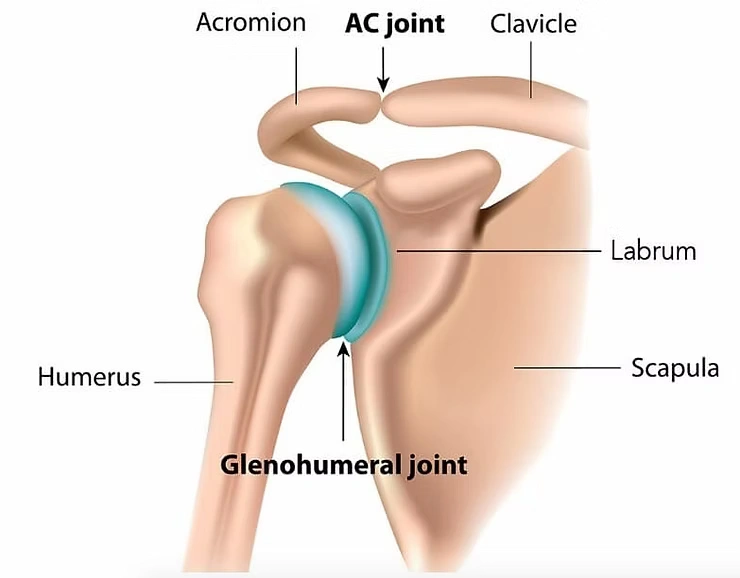

A frozen shoulder is a term that physiotherapists refer to medically as Adhesive Capsulitis. The shoulder joint or glenohumeral joint is surrounded by a capsule that is comprised primarily of connective tissue that helps maintain the stability of the shoulder joint.

Unfortunately with a frozen shoulder, the capsule becomes inflamed and thickened and causes the shoulder to be painful with certain movements. The classical sign that a patient may have adhesive capsulitis is the shoulder has reduced both active and passive range of motion specifically with horizontal abduction, reduced flexion and reduced external rotation. Many patients complain that the shoulder is painful at night while sleeping and experience disturbed sleep.